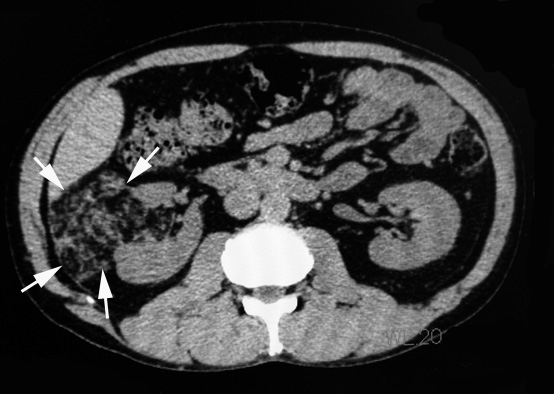

右腰痛のため受診。精査で右腎に出血をともなう直径7cmの腫瘤を認めた。angiomyolipomaの出血と診断し, 出血の消失をまって右腎摘出術をおこなう。

- 典型的angiomyolipoma(AMLoma)は腎実質の一部を置換する腎内腫瘍である。病変サイズは大小さまざまで被膜病変は数ミリを越すことはまれな一方, 腎実質腫瘍は最大径が3-20cm(平均9.4cm)となり大型の腫瘤は周囲の構造を圧迫することになる。通常は単発であるが20%の例では多発する。

- AMLomaは境界のある腫瘍であるが, 被膜はもたず隣接する腎実質を犠牲にして腫大する傾向があるため腎実質は腫瘍に取り囲まれ腫瘍内部に取り残されることになる。 取り込まれた腎尿細管は拡張して嚢胞を形成する。ひどい場合には多嚢胞腎様になりtuberous sclerosis患者さんに多い。

- 通常分葉状で黄色, わずかに油脂状の腫瘤。平滑筋が主要成分の場合は灰白色で硬い。出血はよく起こり症状のある例ではとくにありふれた現象である。腫瘍全域におよぶ出血もありうる。